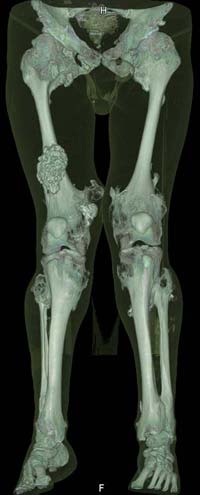

Oбратился больной 30 лет с хондродисплазией, множественными деформациями и экзостозами. Сгибательно-приводящие контрактуры Т/Б сустав, поясничный лордоз.

Интелектуально развит, работает програмистом. Болей нет. Анализы крови в пределах нормы, понижен кальций (общий Ca 1.62, N от 2.3 до 2.75;ионизорованный 0.67, N от 0.7 до 1.07) и щелочная фосфотаза -7.9. По данным КТ, оптическая плотность диафизов 150 - 200 NU (N в его возрасте 300 -350NU) метафизарный остеопороз от 100NU до отрицательных величин - 80 NU.

30 years old male with chondrodysplasia and multiple exostoses admitted.Multilevel deformities, flexion-adduction limitation of hip ROM, lumbar lordosis. Intellectually developed, working in some software company. Painless. Blood tests are normal, except low Calcium (total serum Ca 1. 62, N is 2.3 - 2.75; ionized 0.67 N is 0.7 -1.07) and low alkaline phosphatase 7.9. Diaphysis bone density is about 150 - 200 NU (N in his age is 300 - 350NU). Metaphis osteoporosis is from 100NU to minus 80 NU.

The x-ray is satisfactory for analysis. In The AP view, The knee and ankle should be exactly anterior and the patella should be facing forward, then we can measure the deformity in the AP. Another lateral view of the whole lower limb should be taken, so we can correct 6 dimensions (X, Y and Z axes and Alpha, Beta and Gamma rotation).

But it seemes to me that he has distal femoral valgus and may be also distal tibial. But anyway, we have to measure a good x-ray (lateral distal femoral angle, Medial proximal tibial angle and also the distal tibial angles).

Somtimes there are many deformities in the same lower limb. I do not like to make it sophistacted and correct everything, but just correcting the biggest deformity will make the alignment much better and the patient will be happy with the least risk and least duration of operation.

After Dr Elbatrawy saw the CT scans he added - the case has multible exostosis and the ulna also may need lengthening on both sides; he will need follow up, as one of the multible exostosis may transform to Chondrosarcoma on top of its cartilagenous cap. It is a common problem associated with this condition.